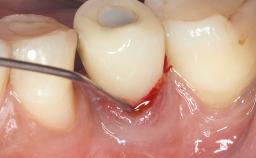

A 37-year-old male patient was referred to the Department of Periodontology at the University of Bern, Switzerland, by a private dentist. Tooth 21 had been lost due to trauma and had been replaced with an implant and a cemented single crown. The tapered-effect tissue-level implant had a diameter of 4.1 mm, a length of 12 mm, and a sandblasted and acid-etched (SLA) surface (Straumann Dental lmplant System; Institut Straumann AG, Basel, Switzerland). The metal-ceramic crown had been cemented permanently, leaving a submucosal gap between the implant shoulder and the crown margin. Absence of marginal bone loss apical to the polished transmucosal neck of the implant could be observed .